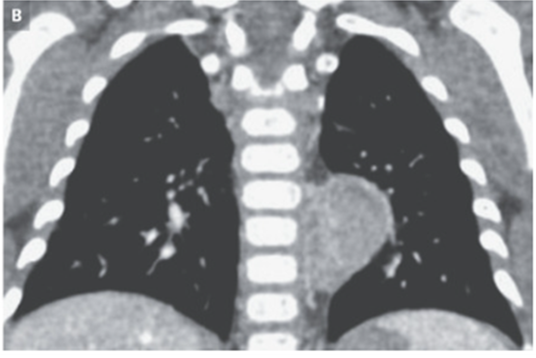

胸部X-p施行。心臓とはシルエットサイン陰性、脊椎とシルエットサイン陽性の腫瘤を認めた。

精査のためCT施行。後縦隔腫瘤が示唆された。